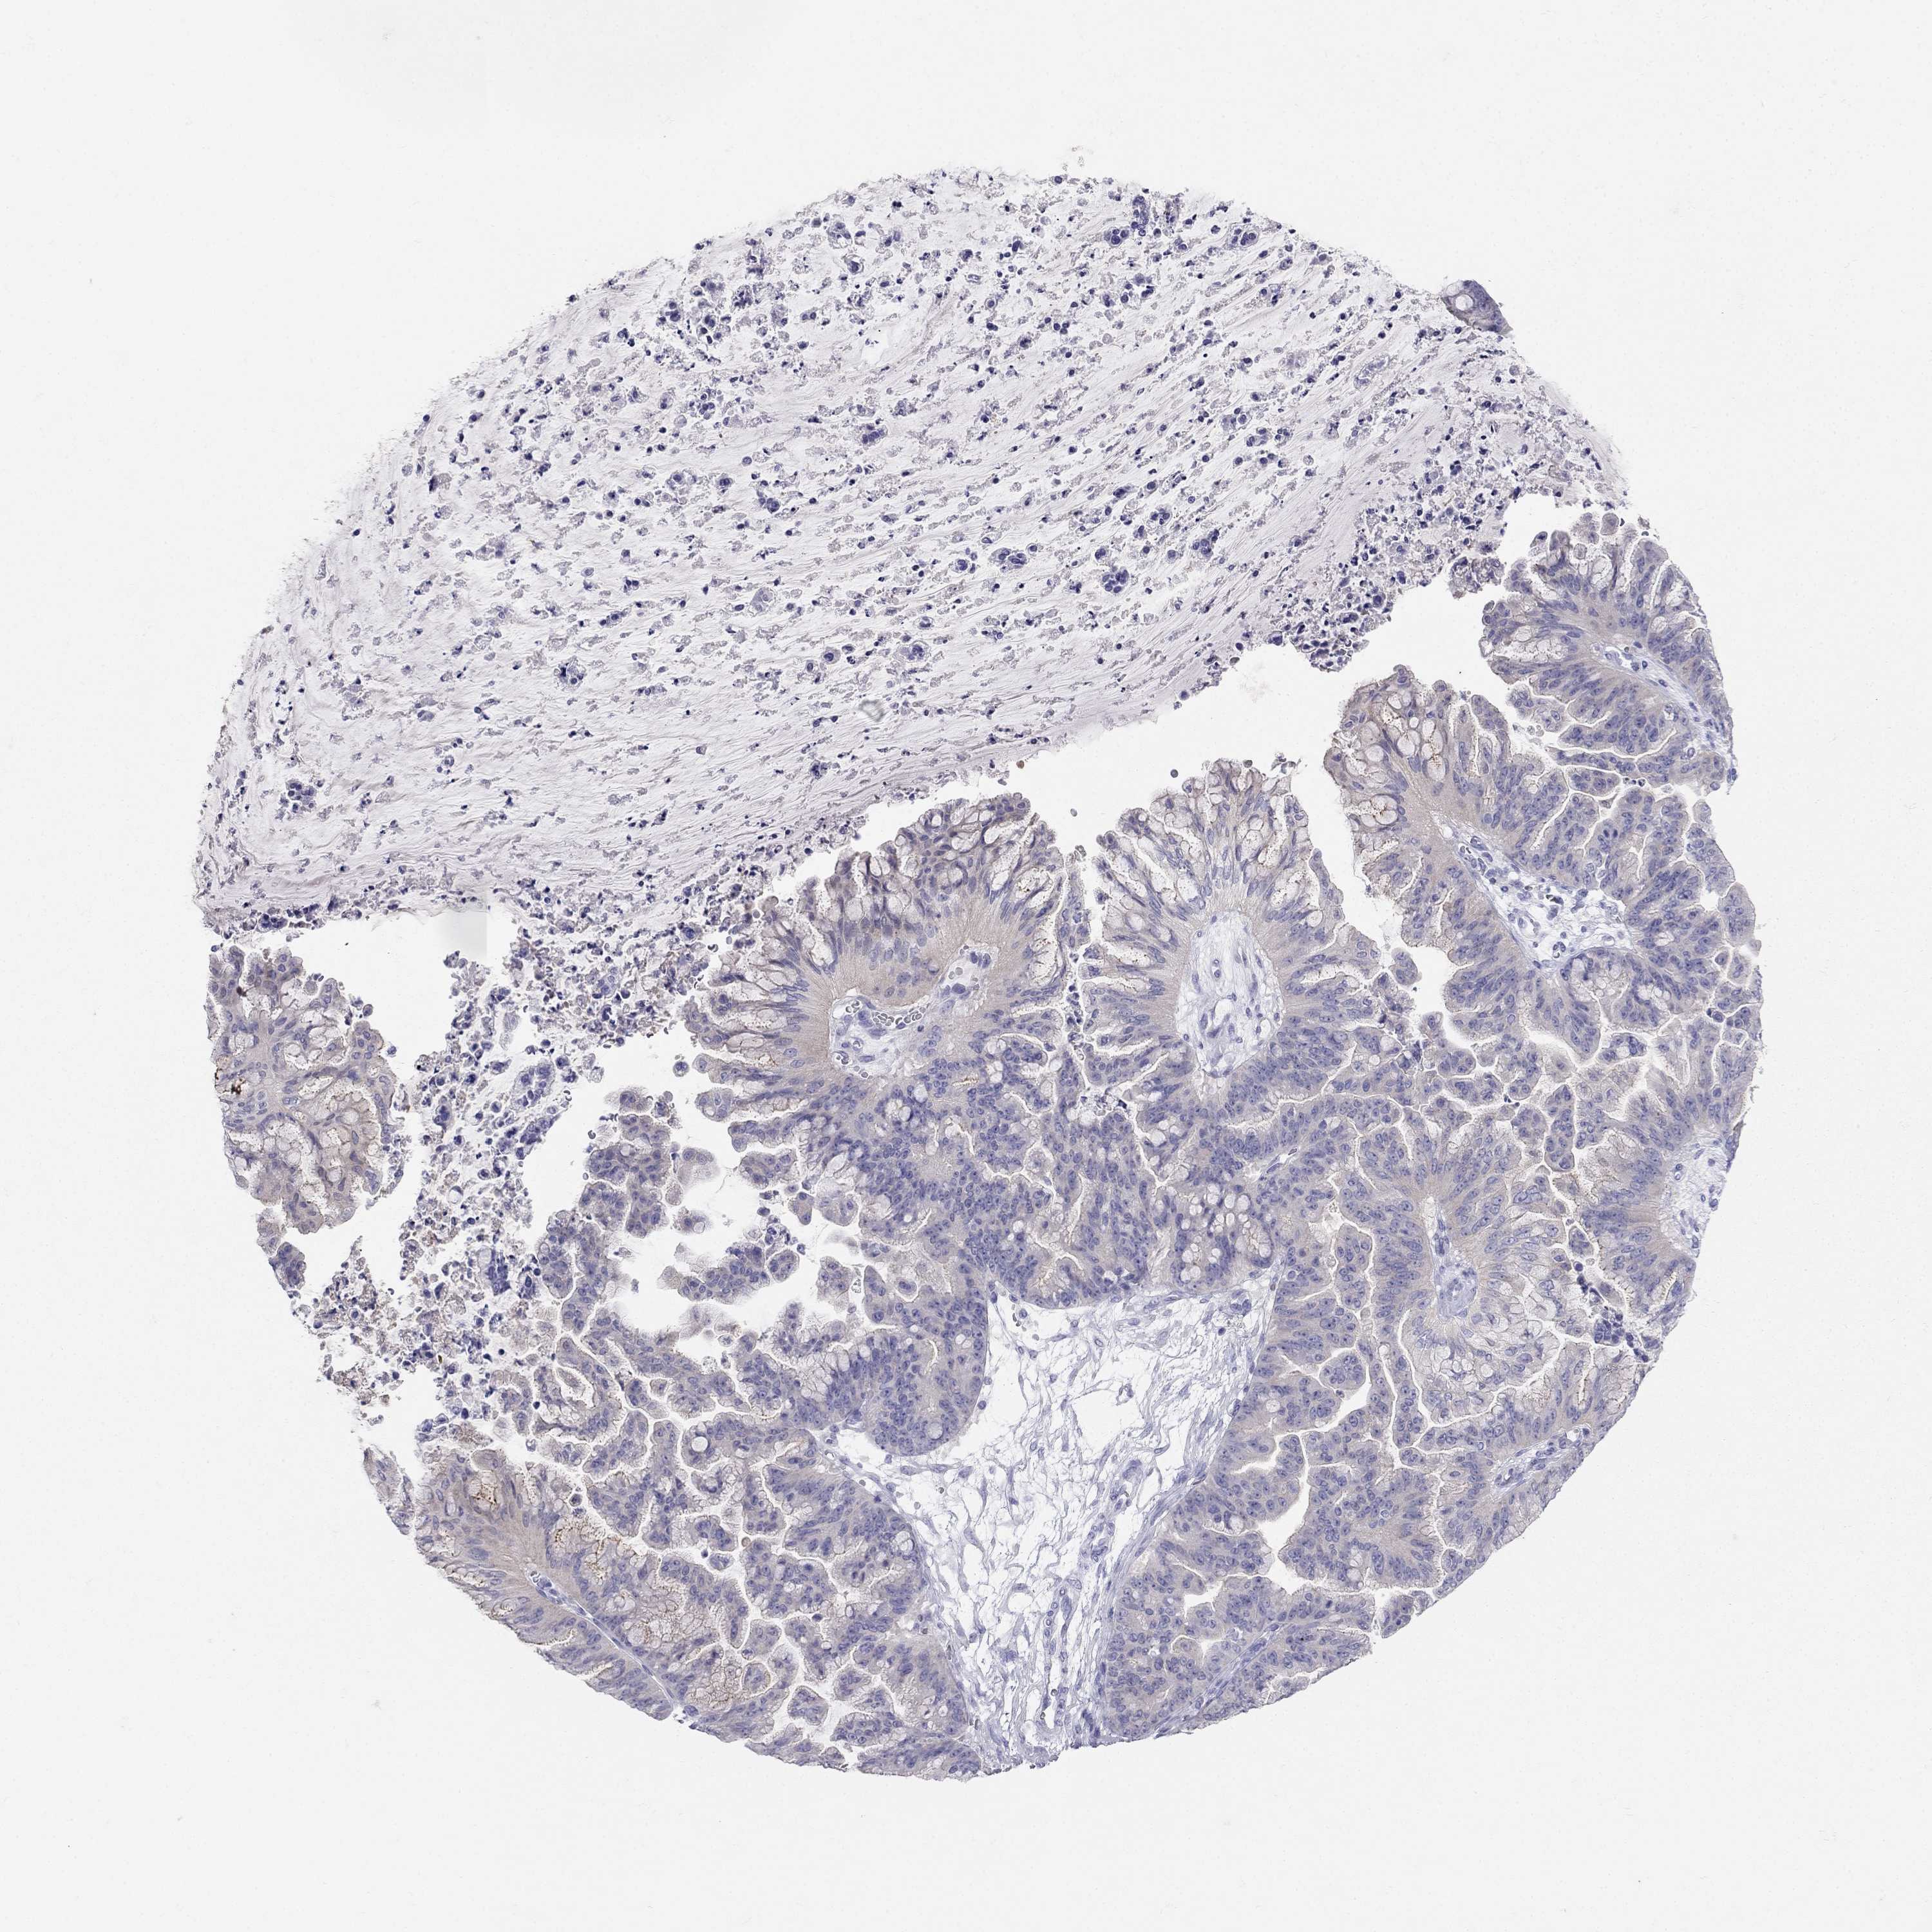

RFLNA